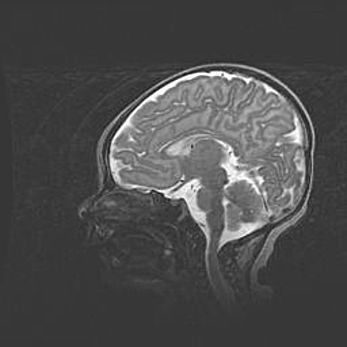

Лейкомаляция с кистозно-глиозной дегенерацией головного мозга.

Возраст: 2 месяца 25 дней

Вес: 6400 г

Окружность головы: 40 см

Срок гестации: 41 неделя

Лейкомаляцию относят к ишемически-гипоксическим повреждениям головного мозга, диагностируемым у новорожденных. При лейкомаляции в головном мозге обнаруживают очаги некроза, возникшие после тяжелой гипоксии и нарушения кровотока. В процессе морфогенеза очаги проходят три стадии: 1) развития некроза, 2) резорбции и 3) формирования глиозного рубца или кисты. Перивентрикулярная лейкомаляция (ПЛ) встречается примерно в 12% случаев среди новорожденных, обычно – у недоношенных детей, причем, частота ее зависит от массы, с которой младенец появился на свет. Наибольшее число малышей страдает лейкомаляцией, если масса при рождении 1500-2500 г.